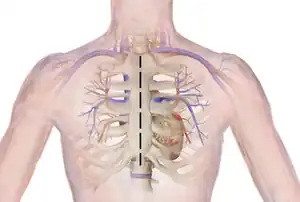

Technique

Before the operation, preparations include transthoracic echocardiography and measurements of the ascending aorta and the pulmonary valve.[10] Under general anaesthesia, the chest is cut open in the midline.[5] The heart and aorta are exposed before the heart is temporarily stopped and its function taken over cardiopulmonary bypass.[5] Subsequent steps include removing the diseased aortic valve and mobilizing the coronary arteries, followed by harvesting and preparing the person's own healthy pulmonary valve, before implanting it within the left ventricular outflow tract, the exit of the left side of the heart (where the aorta begins).[2][10] Then the coronary artery is reimplanted, before the pulmonary homograft is implanted in the right ventricular outflow tract, the exit of the heart's right side (where the pulmonary artery begins).[2][10] The pulmonary autograft is joined with the ascending aorta.[2][10]

Open Heart Surgery Incision